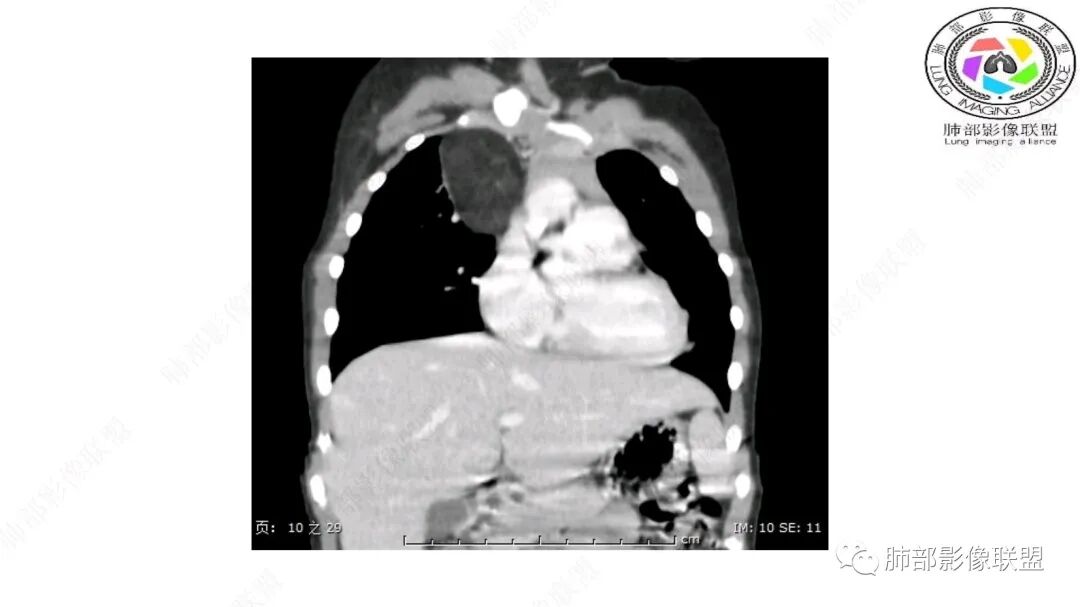

右上纵隔混杂密度肿块,边缘光整,与纵隔分界清,其内多发脂肪密度,增强无明显强化,其内血管穿行,考虑纵隔脂肪母细胞瘤,鉴别畸胎瘤,脂肪肉瘤。

三岁小儿,右侧纵隔巨大脂肪密度肿块,肺动脉穿行其中,密度欠均匀,未见明确实性成分,纵隔脂肪母细胞瘤,冬眠瘤鉴别纵隔脂肪增多症(多弥漫对称)。

患儿3岁 咳嗽检查发现纵隔占位。右肺上叶受压表现,占位以脂肪组织密度为主,似见分隔,首先考虑为脂肪母细胞瘤,鉴别脂肪瘤,畸胎瘤。

病灶属于交界区,主体位于肺内,占位效应明显,前方突入胸壁,胸腺受压变形,胸膜显示欠清楚;病灶包绕上叶肺动脉;似乎有体动脉供血。符合肺内的点:包绕上叶肺动脉分支;符合纵隔的点:前方似乎突入胸壁,与胸腺关系比较密切,但是与上腔静脉的关系提示病灶不支持纵隔来源,前纵隔的常规会将上腔静脉受压后移、外移,这是不符合的。

手术记录:见右肺上叶肿物,肿物与右肺上叶关系密切。与纵隔无粘连,逐步分离肿物,见肿物大小约6cm*5cm,边界清楚,于右肺上叶粘连,边界清楚,肿物包绕右肺上叶血管及支气管。超声刀逐步游离肿物,完整切除肿物,右肺上叶肺组织无破溃,表面无出血。

1.右上肺-纵隔交界区巨块影,主体位于右肺一侧,紧贴胸腺、头臂干、右锁骨下动脉、上腔静脉、奇静脉等,不能分离,但病灶整体边界清楚。注意上述相邻腔静脉等结构未见受压变形,纵隔亦未见明显向左推移,至少提示两点:

2.肺动脉穿行也许是肺内来源最重要支持点!

脂肪母细胞瘤由成熟程度不同的脂肪组织、纤维间隔、黏液基质、小血管丛等间质成分组成,以脂肪组织与黏液样基质为主,其影像学表现取决于上述组织成分。典型的CT和MRI表现为:前后纵隔均可发生,常见于前纵隔;肿块大小不一,直径多在3cm~7cm,密度均匀,CT值呈水样或脂肪密度,脂肪组织密度或信号为主的肿块,其内密度或信号不均匀,可见粗细不一的分隔影,且有结节、片状影,后者可呈轻中度强化;结节状肿瘤包膜完整;弥漫性者包膜不明显,常呈浸润性生长;周围结构为受压和推移改变,可有少量胸腔积液,淋巴结无增大。